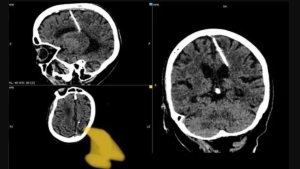

Una anciana rusa vivió 80 años con una aguja en el cerebro